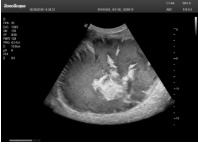

4容積探頭

積探頭是在二維圖像的基礎(chǔ)上,將連續(xù)采集的空間分布位置,經(jīng)過計(jì)算機(jī)重建算法,從而獲得完整的空間形態(tài)。

適用于:胎兒面部、脊柱和肢體等。

優(yōu)勢(shì)特點(diǎn):快速獲取、掃查連續(xù)均勻、解剖結(jié)構(gòu)顯示為容積數(shù)據(jù)、準(zhǔn)確進(jìn)行容積測(cè)量。